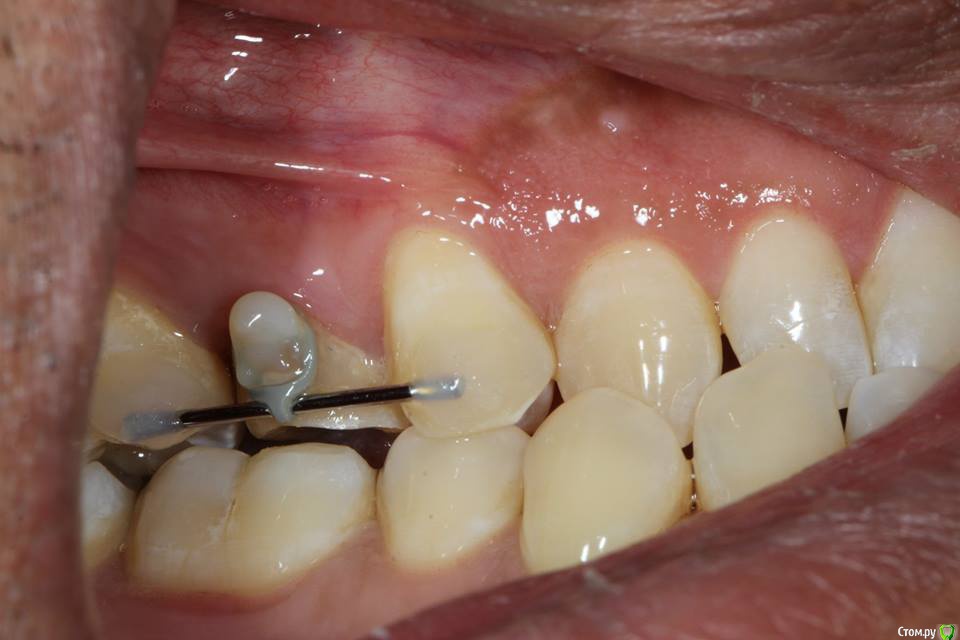

Kolchanov Опубликовано 23 июня, 2015 Поделиться Опубликовано 23 июня, 2015 Экструзия одиночного зуба для получения хоть какого-нибудь феррула. Подозреваю, что процедура не очень сложна и вполне модет быть освоена простым терапевтишкой, т.е. мной. Был бы очень благодарен, если бы кто-нибудь накидал своих мыслей по этому поводу, а еще лучше и фоток. И, конечно же, перечисление материалов. В одной из клиник, где я работаю, делают так иногда.После удаления штифтового зуба имеем поддесневой дефектhttp://s010.radikal.ru/i311/1506/49/4f3a03a5b53b.jpghttp://s010.radikal.ru/i313/1506/55/c752a532f478.jpgПациентка пожелала зуб сохранить. Теперь его тянут. И пятерочку еще в придачу.http://s014.radikal.ru/i327/1506/75/e9897bfb0e24.jpghttp://i024.radikal.ru/1506/99/1f1453b881ef.jpghttp://s017.radikal.ru/i434/1506/ea/caf4284659b4.jpghttp://s018.radikal.ru/i522/1506/ae/b2b54bddcdb8.jpghttp://s015.radikal.ru/i331/1506/7c/0efe752f8c35.jpgПока ничего сложного не вижу.У меня сейчас есть похожий случай. Но, послать в Москву... Не поедут. А на местного ортодонта как-то надежды мало. Я потом залью сюда фотки со своими мыслями. Может кто что присоветует...Спасибо! 1 Ссылка на комментарий

krokomot Опубликовано 23 июня, 2015 Поделиться Опубликовано 23 июня, 2015 Экструзия одиночного зуба для получения хоть какого-нибудь феррула. Подозреваю, что процедура не очень сложна и вполне модет быть освоена простым терапевтишкой, т.е. мной. Был бы очень благодарен, если бы кто-нибудь накидал своих мыслей по этому поводу, а еще лучше и фоток. И, конечно же, перечисление материалов. В одной из клиник, где я работаю, делают так иногда.После удаления штифтового зуба имеем поддесневой дефект Пациентка пожелала зуб сохранить. Теперь его тянут. И пятерочку еще в придачу. Пока ничего сложного не вижу.У меня сейчас есть похожий случай. Но, послать в Москву... Не поедут. А на местного ортодонта как-то надежды мало. Я потом залью сюда фотки со своими мыслями. Может кто что присоветует...Спасибо!Ох и любят у нас врачи заниматься вот таким лепиловом)))) Инженера в себе не скроешь)) Почему не с бреккетами? Приклеили несколько, дугу, цепочку проволку, что угодно, все же проще и предсказуемее (и быстрее) Ссылка на комментарий

krokomot Опубликовано 25 июня, 2015 Поделиться Опубликовано 25 июня, 2015 (изменено) а вот вам моя идея: через 2 проволочные балки сверху ортодонтическую цепочку за ваши зацепы))http://s017.radikal.ru/i431/1506/b6/5d74d8cbbd5a.jpgплюс конструкциив выравнивании силы оральной и вестибулярной)) Изменено 25 июня, 2015 пользователем krokomot Ссылка на комментарий

Kolchanov Опубликовано 25 июня, 2015 Автор Поделиться Опубликовано 25 июня, 2015 а вот вам моя идея: через 2 проволочные балкиВот! Именно так я и собирался сделать, если ортодонт местный сольется. Только я не знаю что такое цепочка ортодонтическая. Хотел просто тягу эластичную какую-нибудь кинуть. Типа кольца сепарационного. Ссылка на комментарий